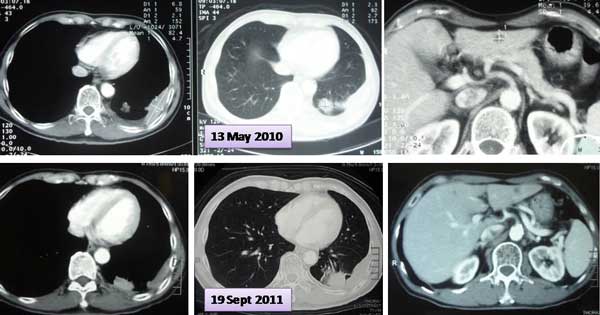

Whole body PET Scan done in Hospital C, 21 August 2018.

- metabolic activity node see in the left (1.3 cm) side of the neck.

- metabolic activity left axillary lymph node (0.6 cm).

- FGD-avid mass (4 cm) seen in the apical segment of the lower lobe of left lung. This is larger and has more metabolic activity compared to the previous PET CT on 18 Jan. 2018.

- metabolic active nodule (1.9 cm) seen in the posterior segment of the upper lobe of right lung – not seen in the previous scan.

- another metabolic active nodule (1.7 cm) seen in the posterior basal segment of the lower lobe of the left lung — not seen in the previous scan.

- a few 2-5 mm, non metabolic active nodules seen in the right and left lungs. These are not seen in the previous scan.

- increased metabolic activity seen in the left adrenal gland (1.4 cm).

- metabolic active lesions seen in the spine of C7 and T1. These re larger and more metabolic active compared to the previous PET CT scan.

- metabolic active bony lesions seen in the spine T12, left sacrum and medial wall of the left acetabulum. These are not metabolic active in the previous scan.

You don’t need to be a doctor to know that FY is getting worse, not better, after taking Tarceva.

The numbers above clearly showed that Tarceva was gradually losing its effective after five months!

In August 2018, the oncologist told FY that Tarceva was not effective anymore. He has to switch to i/v chemotherapy and radiotherapy. A cycle of chemo would cost RM12,000.